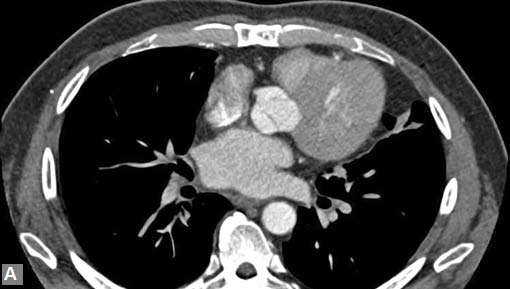

Filling defects (Figs 16A and B) may be seen in main

pulmonary artery (MPA), left pulmonary artery (LPA) and

right pulmonary artery (RPA), interlobar artery, segmental

divisions (Figs 17A and B). On occasions, detection in distal

parts of segmental divisions is difficult. This can be further

confounded by motion artifacts, non- or minimally opacified

accompanying pulmonary veins.